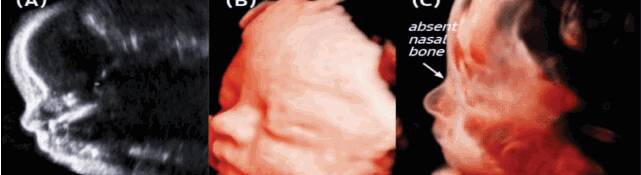

胎儿鼻骨在超声上显示为鼻梁内一条有回声的细线,检测的最佳时间为孕11~13+6周。